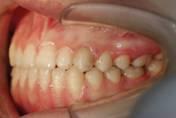

一般來說牙齒咬合不齊主要是指上頜牙齒正中線餘下與牙齒正中線不對齊,下頜牙齒一側向里倒,其不僅影響牙齒外觀,而且對於口腔功能的正常發揮、以及牙周組織健康及口腔衛生具有很大的影響。可以通過美牙矯正來達到很好的效果。

錯位咬合畸形不僅影響妨礙口腔和面部組織的正常發育,妨礙牙齒及牙周組織的健康,而且影響口腔功能及面容的美觀。